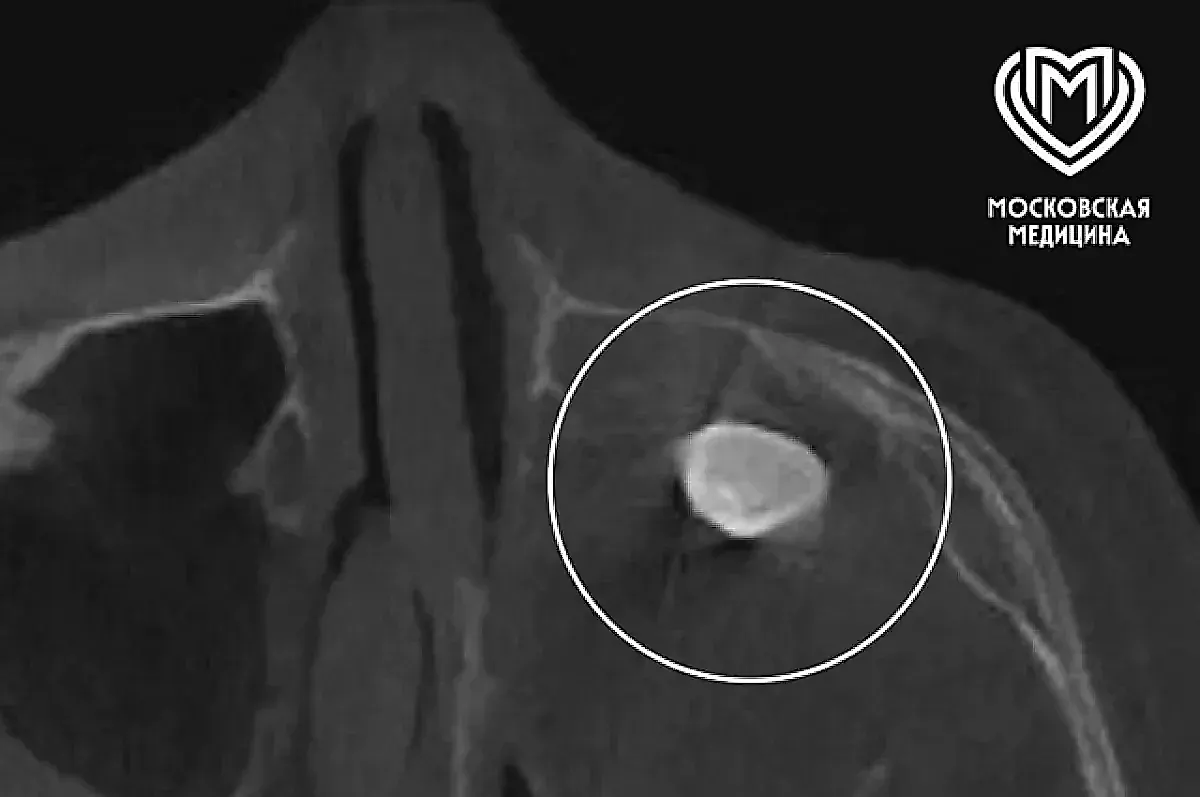

Ранее, при обследовании в частной клинике, у подростка в гайморовой пазухе — это полость в верхней челюсти, связанная с носом — был выявлен сформированный зуб. Такая находка сама по себе редка, но ещё более неожиданным стало предложение удалить его через полость носа. Родители, обеспокоенные этим методом, решили обратиться за второй консультацией в Филатовскую больницу, известную своим опытом в детской хирургии и сложных случаях.

Во время вмешательства медики сделали ещё более удивительное открытие: зуб оказался не просто «заблудившимся» в носу, а частью новообразования. Внутри этого образования и находился тот самый зуб. После проведения гистологического исследования — изучения тканей под микроскопом — выяснилось, что это тератома. Тератома — это редкий тип эмбрионально-клеточного новообразования, которое может содержать элементы тканей, несвойственных для той области тела, где оно расположено. В данном случае тератома была доброкачественной, то есть не представляла непосредственной угрозы жизни, но её размеры и расположение создавали серьёзные проблемы.

Новообразование занимало практически всю левую полость носа подростка, что объясняло стойкую заложенность и асимметрию лица. Интересно, что из-за своих особенностей тератома не была чётко видна на стандартных методах диагностики, таких как компьютерная томография (КТ) и рентген, что усложнило первоначальное выявление. Это подчёркивает важность комплексного подхода и опыта врачей в распознавании таких нетипичных случаев.